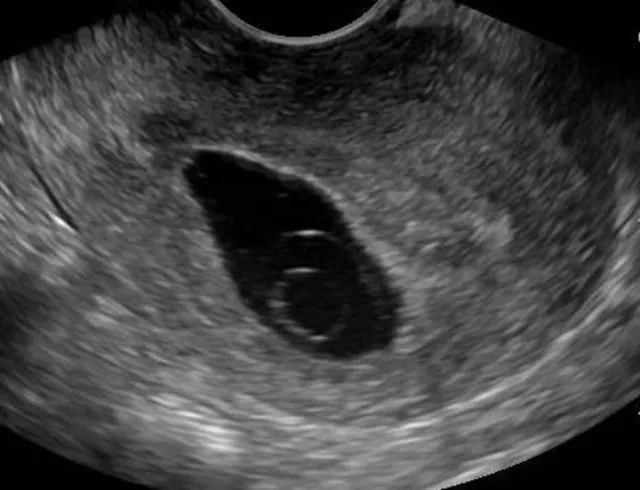

Blighted ovum, atau kehamilan anembrionik, adalah jenis keguguran yang terjadi sangat dini dalam kehamilan. Kondisi ini terjadi saat sel telur yang sudah dibuahi berhasil menempel di dinding rahim, tetapi tidak berkembang menjadi embrio. Akibatnya, kantung kehamilan tetap kosong dan akhirnya menyebabkan keguguran pada trimester pertama.

Blighted ovum biasanya terjadi sekitar minggu keempat hingga kesembilan kehamilan. Dalam perkembangan normal, sel telur yang dibuahi akan berkembang menjadi blastosit dan menempel di rahim. Seharusnya, embrio mulai tumbuh di dalam kantung kehamilan. Namun dalam kasus ini, pertumbuhan embrio berhenti atau tidak pernah terjadi sejak awal.

Tes kehamilan menunjukkan positif, tetapi saat USG tidak ditemukan embrio.

Satu-satunya cara pasti untuk memastikan blighted ovum adalah melalui pemeriksaan ultrasonografi transvaginal, yang menunjukkan kantung kehamilan kosong.

Dokter akan mendiagnosis blighted ovum melalui USG transvaginal antara minggu ke-7 hingga ke-9 kehamilan. Pada usia kehamilan tersebut, embrio seharusnya sudah terlihat. Jika tidak ada embrio di dalam kantung kehamilan, maka diagnosis blighted ovum kemungkinan besar ditegakkan.